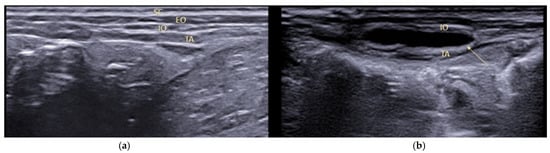

Figure 1.

Lidocaine infiltration on ovarian pedicle during video-assisted OVH (a) and open surgery (b).

Ultrasonographic visualisation of the anatomical structures of the abdominal wall in a dog (SC, subcutaneous tissue; EO, obliquus externus; IO, obliquus internus; TA, transversus abdominis) before (a) and after (b) local anaesthetic injection. The patient in lateral decubitus.